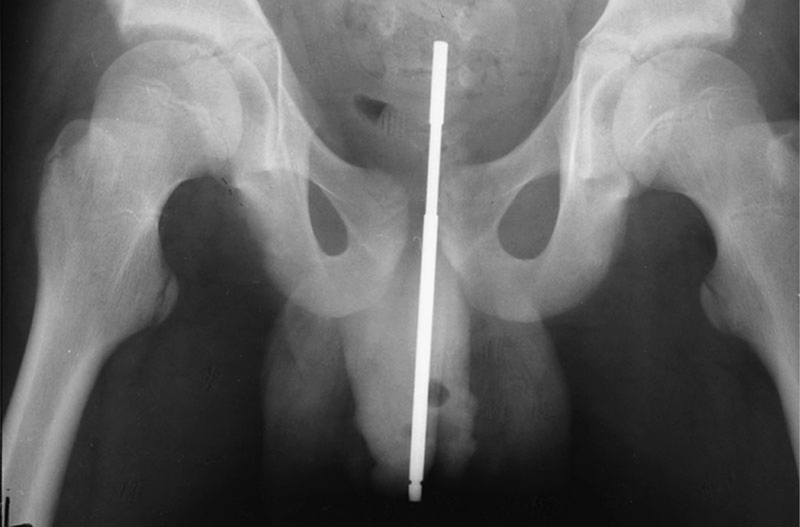

Thông thường, một số hình ảnh X-quang được ghi lại để xác định chính xác vị trí và độ sâu của vật thể lạ. Các vật thể lạ làm từ vật liệu có độ tương phản thấp (ví dụ như nhựa) có thể cần phải siêu âm hoặc chụp CT. Các dị vật trực tràng có thể xâm nhập sâu vào đại tràng, trong một số trường hợp nhất định có thể lan tới góc đại tràng phải.